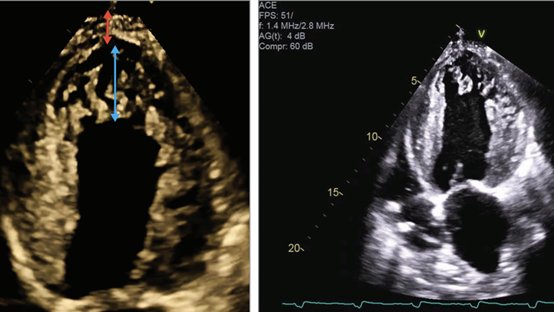

Left Ventricular Noncompaction(? Μη συμπαγές) Cardiomyopathy JAMA Cardiology online May 21, 2025

48 χρονος άνδρας παρουσιάσθηκε στα ΤΕΠ με δύσπνοια και εικόνα shock. Color Doppler. The red arrow indicates the length of the noncompacted LV segment, and the blue arrow represents the compacted segment. For more … Circ Cardiovasc Imaging. 2020;13(1):e009712. OΞΕΙΑ ΘΡΟΜΒΩΣΗ ΤΗΣ ΑΝΩ ΜΕΣΕΝΤΕΡΙΟΥ ΦΛΕΒΑΣ n engl j med 392;20 May 29, 2025